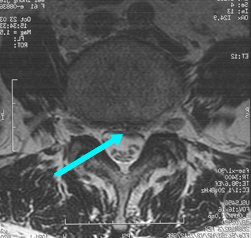

磁共振成像(MRI) 可直接顯示頸椎間盤突出部位、類型及脊髓和神經根受損的程度,為頸椎間盤突出症的診斷、治療方法選擇及預後提供可靠依據。MRI對頸椎間盤突出症診斷的準確率遠遠大於CT和CTM。在中央型和旁中央型頸椎間盤突出症中可顯示清晰影像:(1)中央型:椎間盤從受累椎間隙水平呈團塊狀突出,壓迫頸脊髓前方中央部位,受壓脊髓局部可呈彎曲、變扁或凹陷狀向後方移位,並有信號異常的表現,其中以信號增強為主,有時可見脊髓內空洞影像;(2)旁中央型:椎間盤呈塊狀或碎片狀向後外側突出,壓迫頸脊髓側方和一側神經根,頸脊髓前外側受壓變形,向後方或健側移位,局部信號增強,神經根向後外側移位或影像消失。側方型頸椎間盤突出往往需要結合CTM進行診斷。